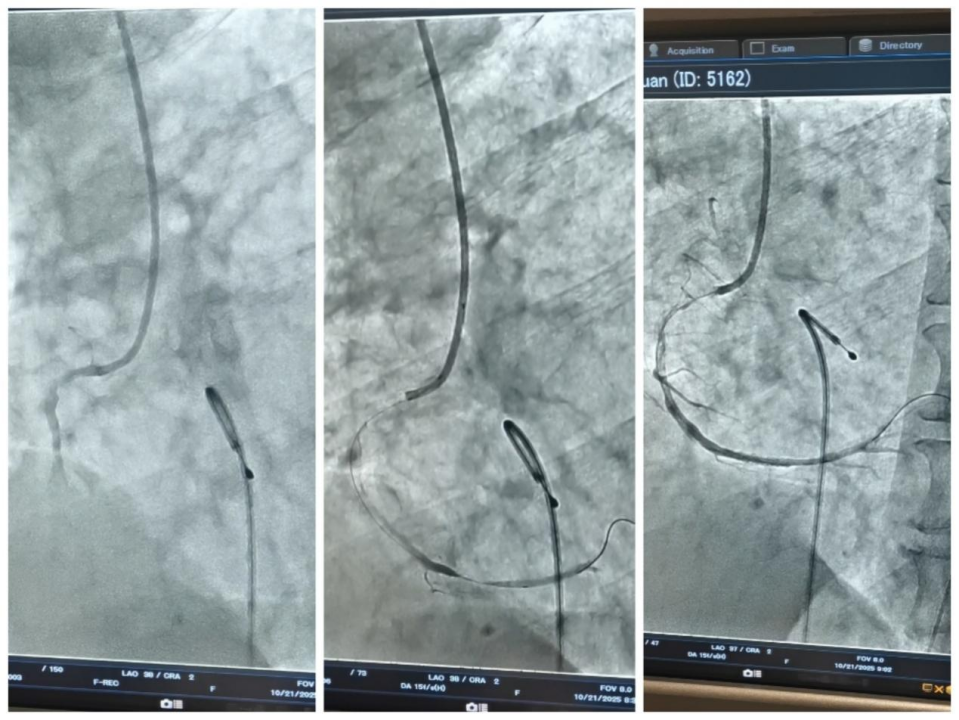

经过充分准备,两位患者先后由李剑锋主任主刀,成功接受了肺癌治疗术。

最终的病理报告带来了最振奋人心的消息,两人的手术标本均达到了pCR,肿瘤细胞已经消失。

△钱大叔治疗前后CT对比

实现pCR,可以说是患者治疗的一个重要节点。李剑锋主任表示,这意味着患者不仅获得了手术的机会,术后也大概率无需再进行放化疗,极大地减轻了身心负担,真正实现了高质量的长久生存。(通讯员 刘裕)